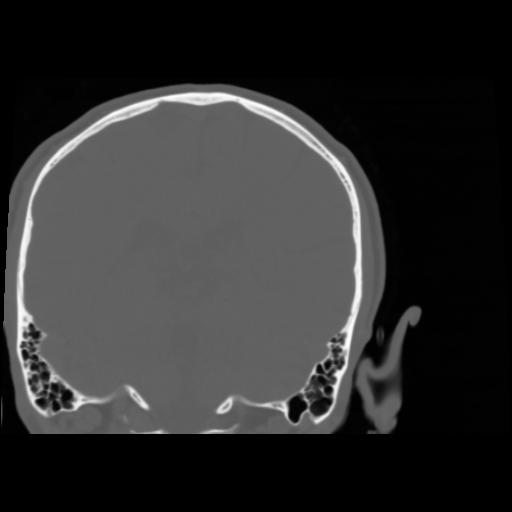

5 CEREBRO,,Coronal,3.000,CEREBRO,Coronal,